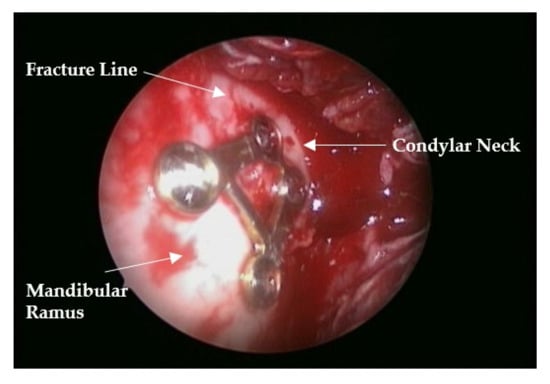

Reliability of a Trapezium Miniplate with Endoscope-Assisted Internal Fixation in Mandibular Subcondylar Fractures: A Three-Dimensional Analysis

2. Materials and Methods